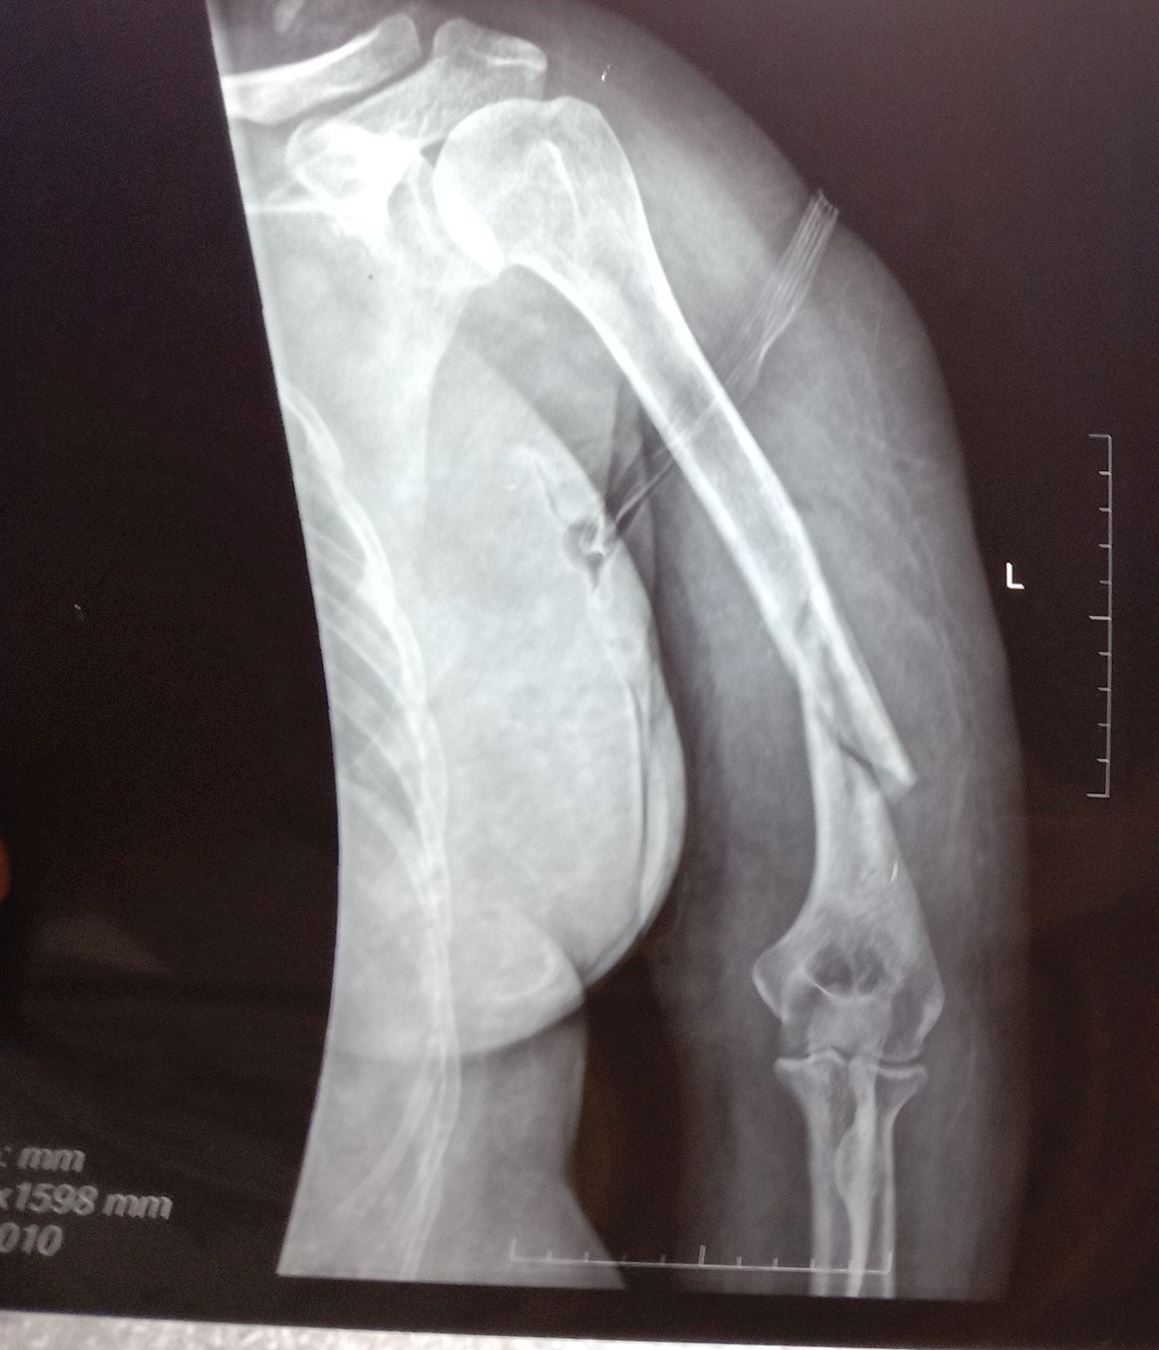

'高翠莲的胳膊被警察扭断'

高翠莲的胳膊被警察扭断

2014年4月21日,公婆把高翠莲送到石林县人民医院,检查被警察打伤不能动的胳膊。拍片子检查结果是;螺旋式粉碎性骨折。医生说,要马上住院,进行手术治疗。家人身上没有那么多钱,只好回家。

2014年4月23日,家人把高翠莲送到昆明市43医院住院治疗,检查结果;螺旋式粉碎性骨折。由于费用太高,还没有做手术,就没有多少钱了,只做了伤情鉴定书,就回家了。

2014年4月26日,伏培生从看守所回到家,又把妻子高翠莲送到石林县天奇医院,检查结果;螺旋式粉碎性骨折。主治医生陈伟告诉高翠莲:政府部门的人员找过他了,你只要承认自己的手臂是不小心摔断的,就可以报销医疗费。高翠莲告诉医生:不说假话,我的手臂就是被警察扭断的。虽然家里困难,家人决定自己凑钱给高翠莲做手术。手术前几天,几个专家来问高翠莲的身体情况,结果发现高翠莲的身体对金属过敏,对针水也过敏,无法治疗,要求转院治疗。家人没有办法,只好回家。